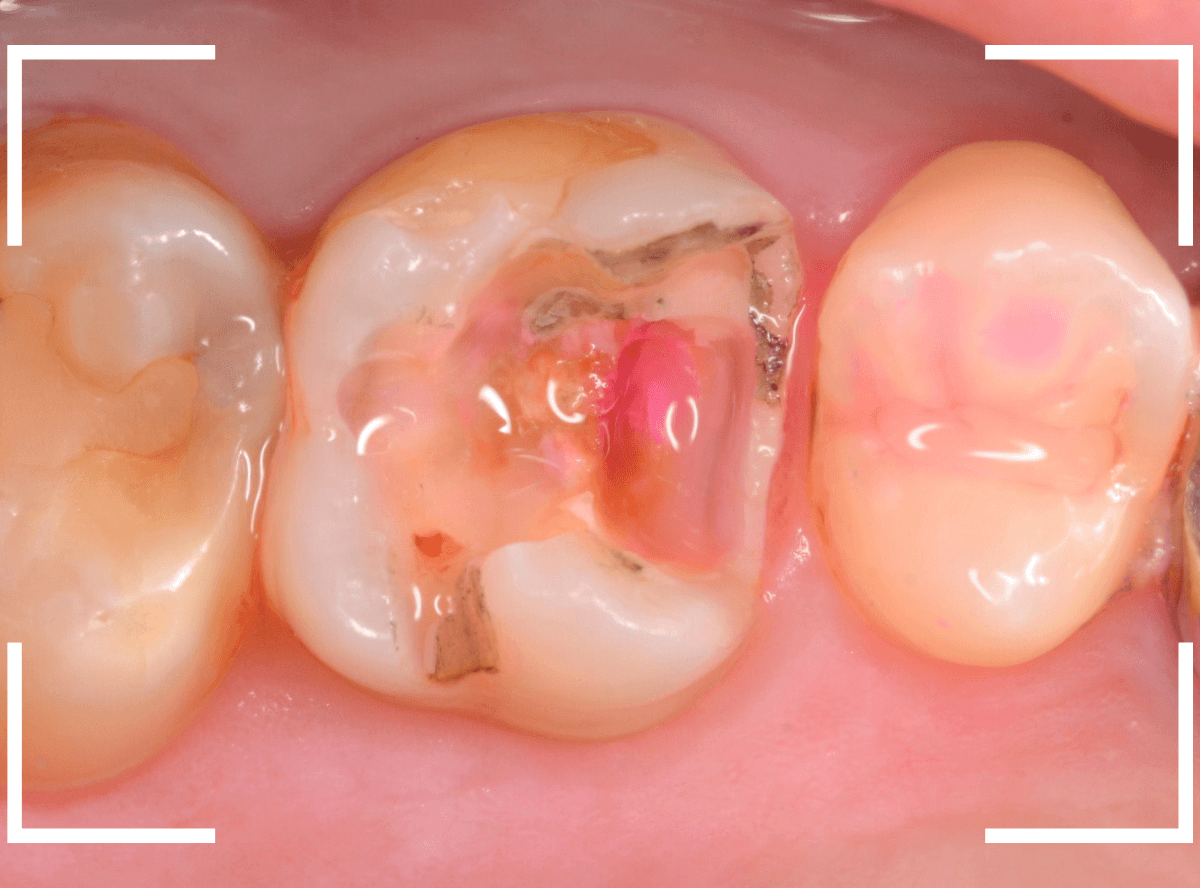

Case.14 インレーの下の歯肉まで広がった虫歯

「下の奥歯が噛むと痛む」という症状で来院された患者さんのケースです。

お口の中の状態を確認すると、奥歯の端に穴が開いているのが見えます。

ここかな?

レントゲン写真で確認します。

やはり、奥歯の端が大きな虫歯になっています。

青いラインが歯の神経、赤いラインが虫歯です。

レントゲン写真上では虫歯が神経まで達しているように見えます。

これは、神経を取らないとダメかもしれません。

中のお薬も慎重に外して虫歯を除去します。

虫歯が深く、歯肉の下まで浸食していましたので、歯肉を部分切除し、虫歯を全て除去したところで、奇跡的に神経スレスレの状態でとどまっていました。

何とも言えませんが、神経を残せる可能性が出てきました。

虫歯が神経まで達していなくても、治療前から自発痛(何もしなくても痛い)があれば、神経をとらなければいけません。

今回は、そこまでの症状がありませんでしたので、患者さんと相談の上、神経を取らずに残す方法で様子を見る事になりました。

痛みが出ませんように。。。